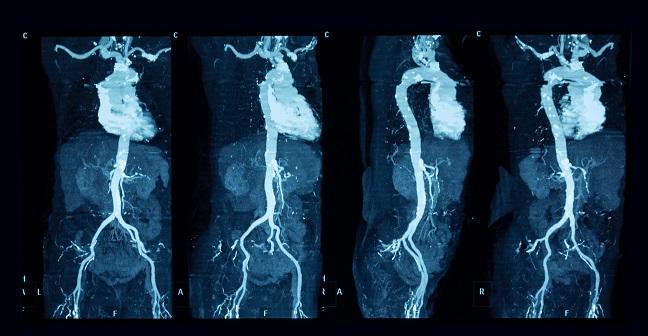

Ever since CTA became the gold standard for assessing the aortic annulus and sizing the valve prosthesis prior to TAVR, the question emerged as to what to do about incidental findings on CTA, Rodrigo Bagur, MD, PhD (University Hospital, London Health Sciences Centre, Canada), told TCTMD. Large-scale data from studies such as SOURCE and PARTNER suggest that approximately two-thirds of patients who undergo TAVR die from noncardiac causes. As such, identifying patients at high risk for early mortality can help guide clinical care, and the presence of incidental findings on CTA may provide important prognostic clues.

The authors conducted a retrospective analysis of 553 patients who underwent pre-TAVR CTA at a single center between 2009 and 2014. They divided patients based on the presence or absence of incidental findings and analyzed up to 5 years of all-cause, non-cardiovascular, and cardiovascular mortality. Their results were published online ahead of print June 29, 2017, in the American Journal of Cardiology.